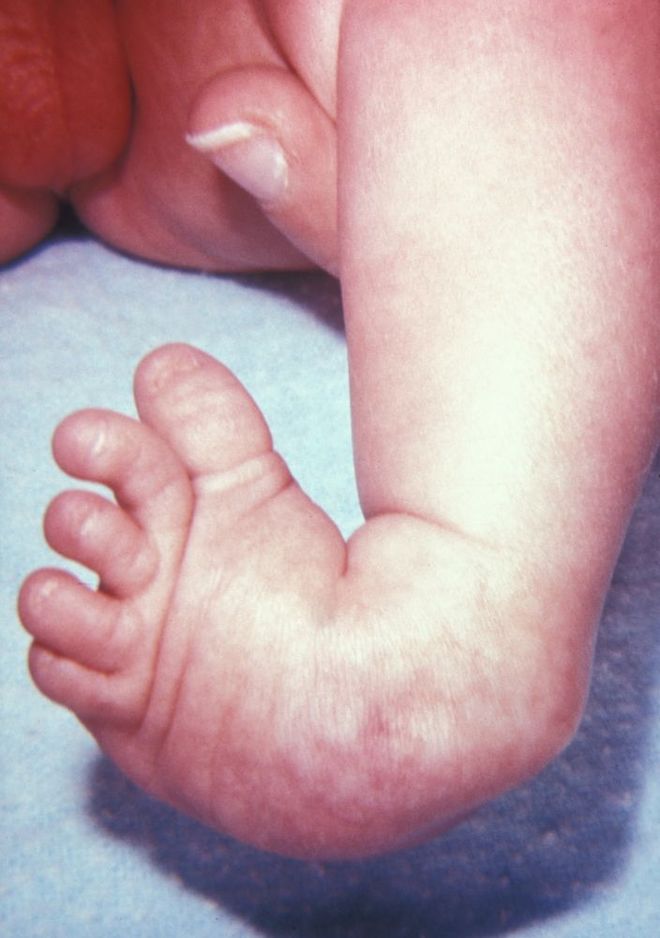

这是一个刚满月的宝宝,摆在医生面前的就这三样东西:一张胸部X光片、一张足部外观照、还有一张血常规化验单。

症状很明显但很分散,就像几个不相干的毛病,这就很考验模型捕捉碎片信息和综合分析的能力。

但WiseDiag V2并没有盲人摸象,而是整体思考:

在胸部X光片,锁定了食管闭锁和半椎体发育异常;

在足部外观照中精准识别了足部的马蹄内翻;

通过化验单的数值和胸部X光片读出了吸入性肺炎的风险。

综合所有信息给出正确的诊断结果——VACTERL联合征。

VACTERL联合征是一种罕见的非随机先天性多系统发育畸形组合,通常由至少三种特定器官缺陷组成:脊柱畸形(V)、肛门闭锁(A)、心脏缺陷(C)、气管食管瘘/食管闭锁(TE)、肾脏畸形(R)和肢体异常(L)

由此可见,WiseDiag V2是一个医疗AI强大的多模态认知底座。